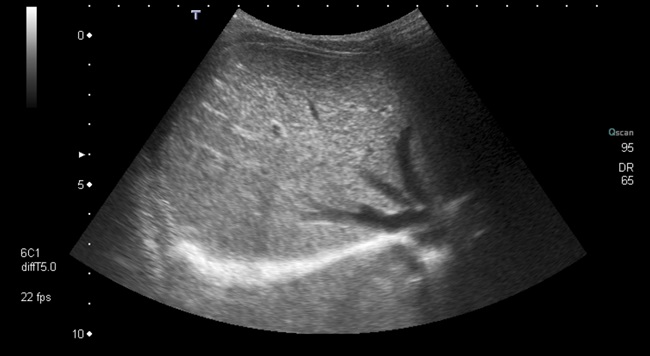

Varón de seis meses, con antecedente de ingreso en la Unidad de Neonatología por prematuridad, que derivan a consulta de Digestivo Infantil por sospecha de agenesia de vesícula biliar visualizada desde la ecografía prenatal de la semana 22. Durante el ingreso en el periodo neonatal se realizan varias analíticas sanguíneas con perfil hepático sin observarse alteraciones y dos ecografías abdominales (a los 10 y a los 28 días de vida) donde no se identifica vesícula (Fig. 1).